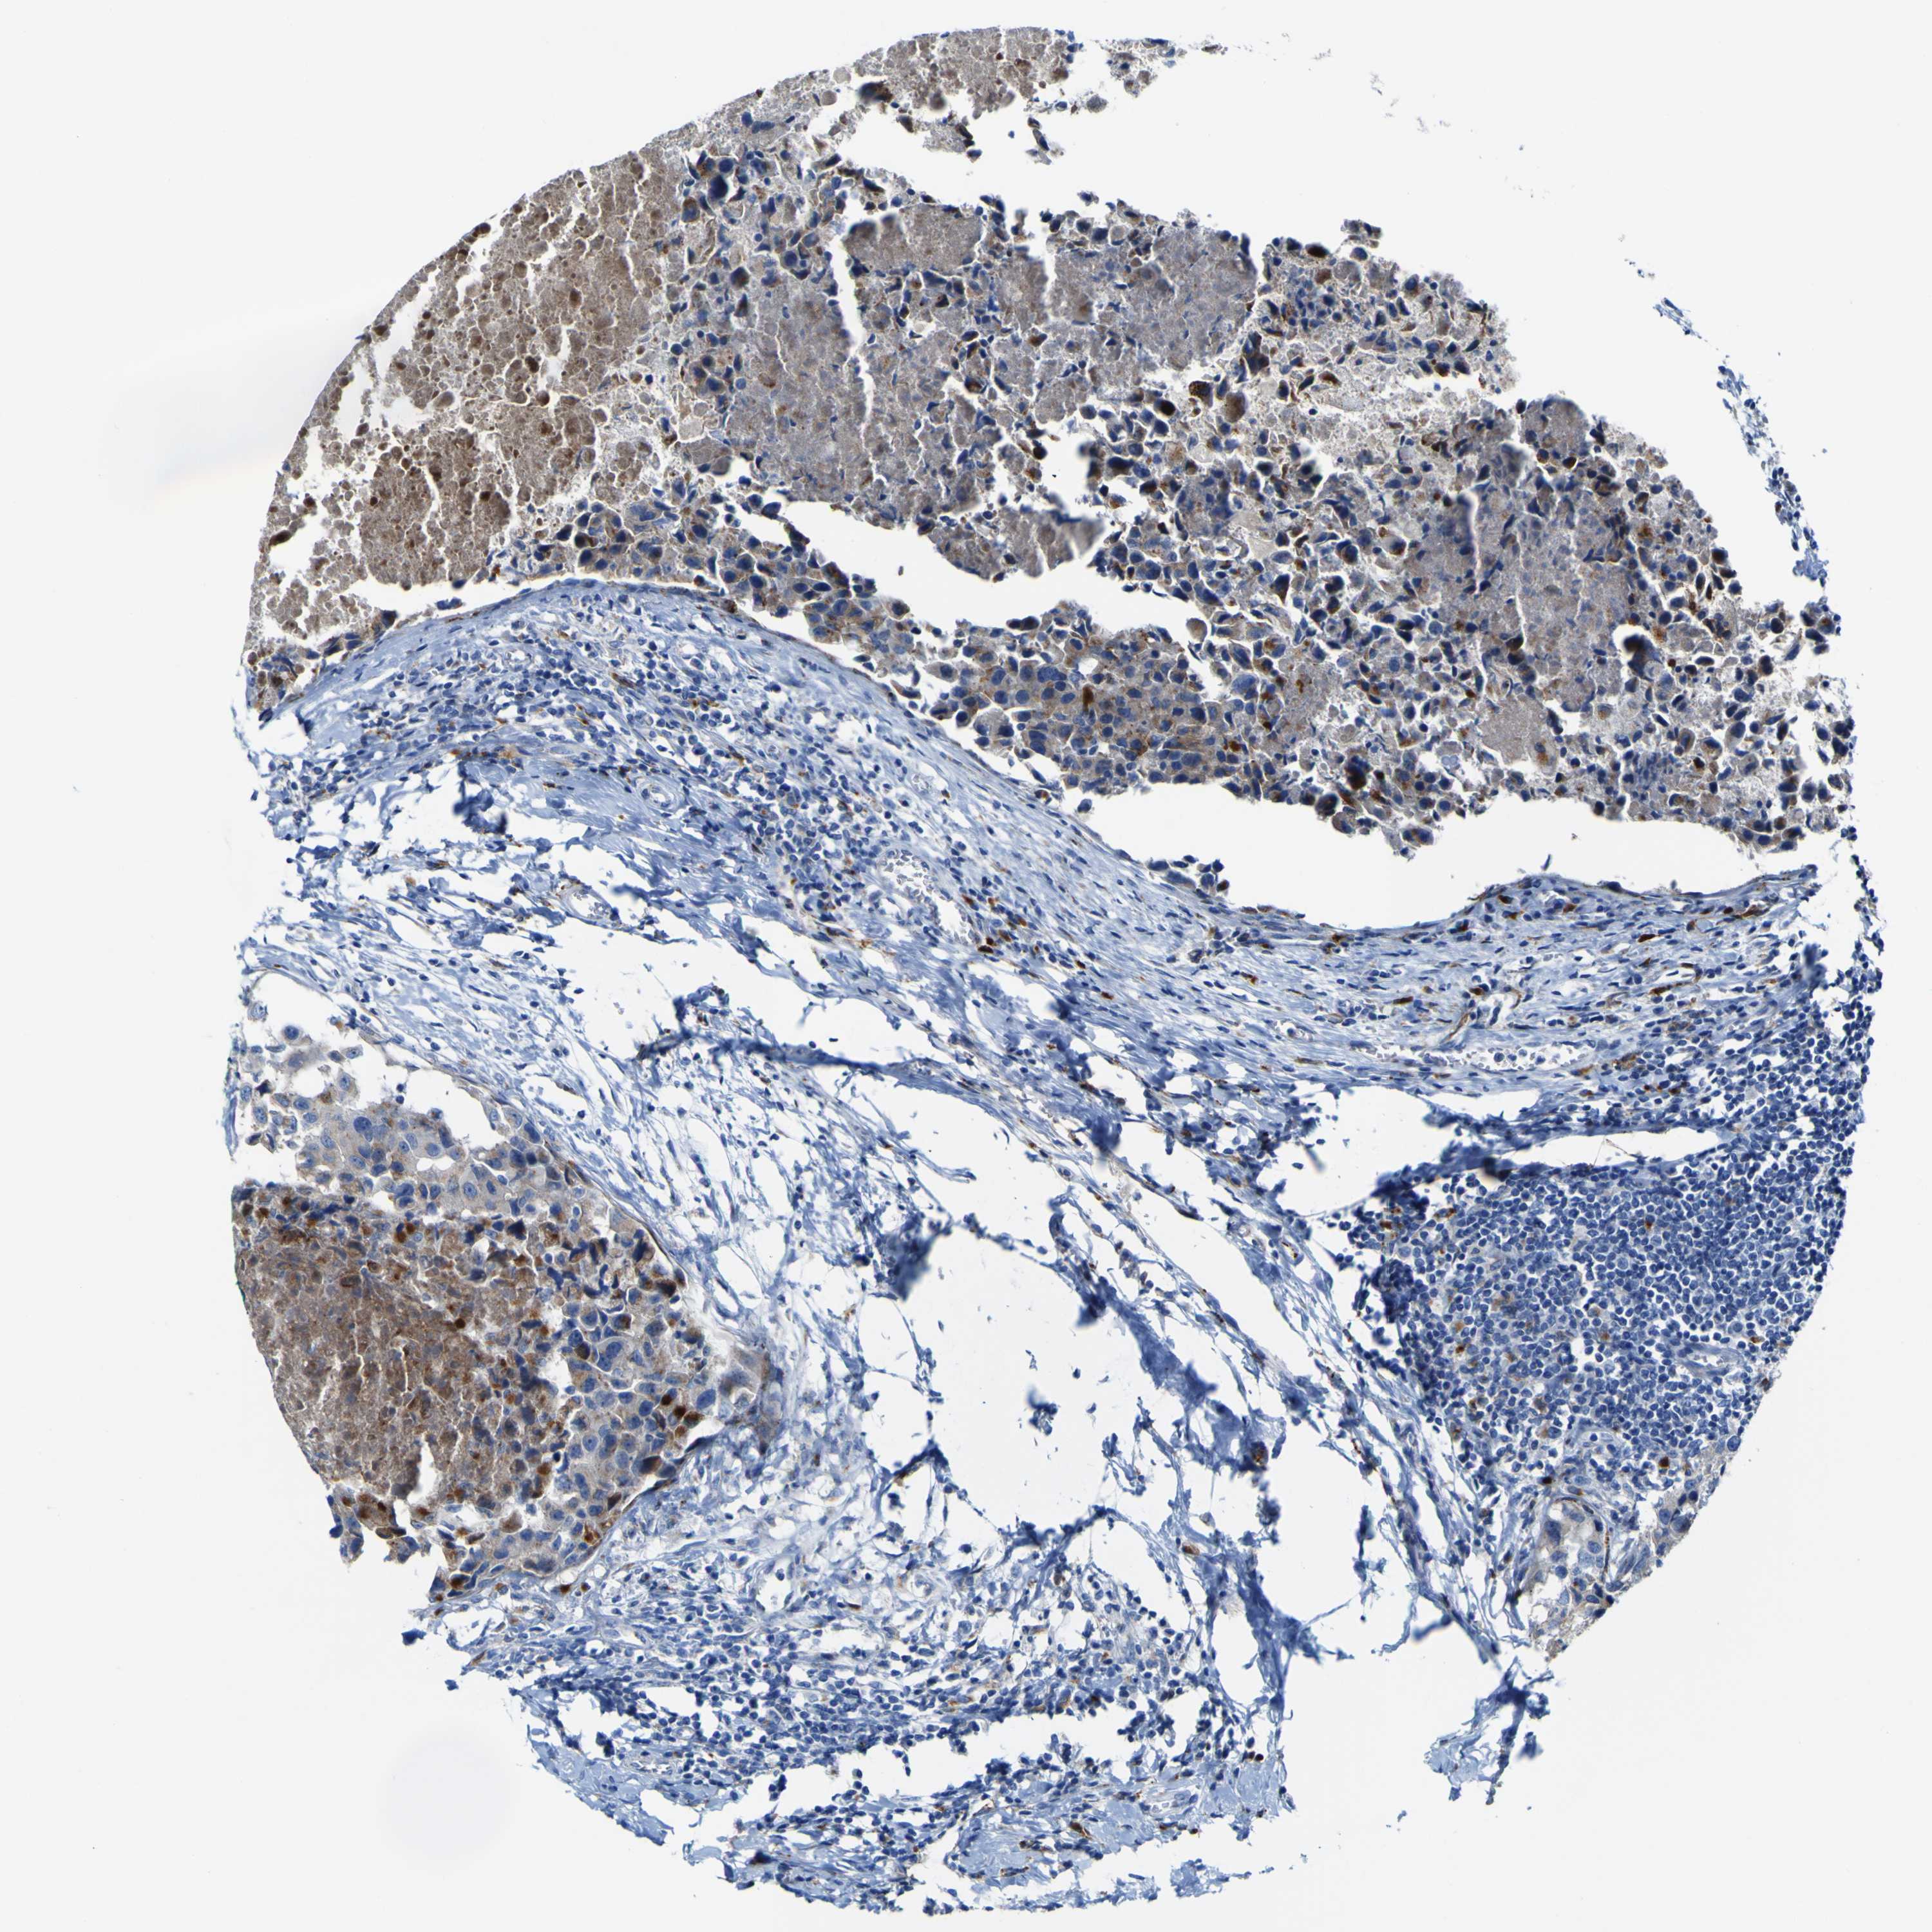

CANCER BREAST CANCER Show tissue menu

BRCA TCGA BRCA VALIDATION PROTEIN EXPRESSION

ANTIBODIES

AND

VALIDATION